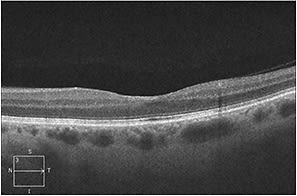

We performed the appropriate baseline tests, including FA and SD-OCT, to rule out any other vision-threatening conditions. As demonstrated in the images, our patient’s retinal hemorrhages improved with observation (Figure 4, page 71). At three months, the patient’s best-corrected visual acuity was 20/25 with almost complete resolution of hemorrhage on fundus examination (Figure 5) and SD-OCT (Figure 6).

Figure 6. At three months, SD-OCT of the left eye showed complete resolution of the subfoveal intraretinal hemorrhage.